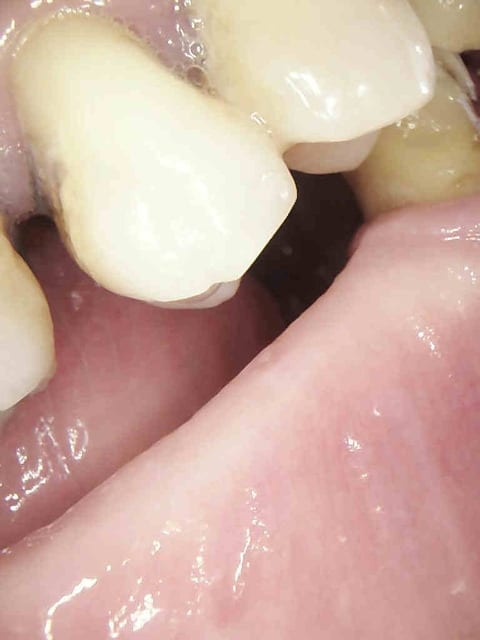

exemple :

Mobilité 31 (motif de la consultation); plan d'occlusion HS ( égression ).

Patient n'ayant pas 10 balles (mais qui travaille pourtant mais au smic malgré la moitié de cotisations sociales il a peanuts de remboursements) avec une mutuelle de merde en plus.

Douleur froid secteur 4. Bilan radio ( coté 6 radios, fuck le pano pas indiqué en plus source d'emmerdes-))))) détartrage.

1 zhor8f - Eugenol

2 efevs3 - Eugenol

3 oiohdr - Eugenol